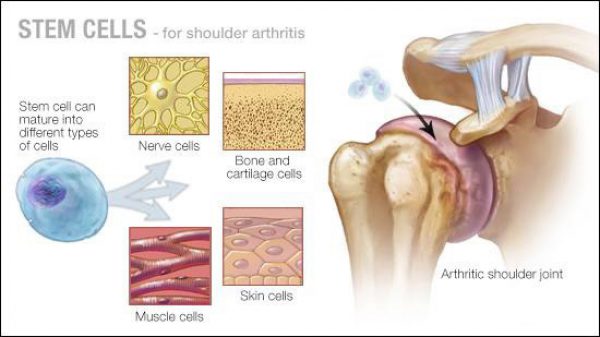

A: สเต็มเซลล์เป็นเซลล์ต้นกำเนิดที่มีลักษณะพิเศษในร่างกายของเรา โดยเซลล์ต้นกำเนิดนั้นมีคุณสมบัติที่สำคัญสองประการ ได้แก่ เซลล์ต้นกำเนิดสามารถทำสำเนาตัวเองใหม่ และด้วยคุณสมบัตินี้เซลล์ต้นกำเนิดเพียงหนึ่งเซลล์จึงสามารถแตกตัวเองออกมาได้อย่างไม่มีที่สิ้นสุด

คุณสมบัติอีกประการ คือ คุณสมบัติในการพัฒนากลายเป็นเซลล์ชนิดอื่น เช่น เซลล์ต้นกำเนิดที่สกัดจากเซลล์ไขมันในห้องปฏิบัติ สามารถพัฒนาตัวเองกลายไปเป็นเนื้อเยื่อกระดูกอ่อนเพื่อสร้างกล้ามเนื้อกระดูกอ่อน หรือกลายไปเป็นเซลล์ประเภทอื่น ๆ อย่างเซลล์ผิวหนังหรือเซลล์กระดูก ในทางทฤษฎีแล้ว

คุณสมบัตินี้สามารถทำให้เซลล์ต้นกำเนิดเกิดการพัฒนาและกลายสภาพไปเป็นเซลล์ประเภทอื่นเพื่อซ่อมแซมได้อย่างไม่มีที่สิ้นสุดเช่นกัน

เซลล์ต้นกำเนิดนั้นสามารถสกัดได้จากแหล่งต่าง ๆ เช่น ตัวอ่อน (embryos) เลือดที่ได้จากสายสะดือ (umbilical cord blood) และเซลล์ของผู้ใหญ่ (adult stem cells) สำหรับ adult stemcells นั้นจะสกัดมาจากผู้ใหญ่แต่เพียงอย่างเดียว ซึ่งเซลล์ต้นกำเนิดที่โตเต็มวัยนั้นจะมีประสิทธิภาพในการพัฒนาเปลี่ยนแปลงตัวเองกลายเป็นเซลล์ชนิดอื่น ๆ

adult stem cells สามารถสกัดมาได้จาก 2 แหล่งใหญ่ๆ คือได้แก่ เซลล์ไขมัน และไขกระดูก

ส่วนที่สกัดจากแหล่งไขมันจะมีชื่อเรียกว่า adipose-derived adult stem cell ซึ่งจะเป็นเซลล์ต้นกำเนิดที่ง่ายต่อการสกัดและมีจำนวนอุดมสมบรูณ์อย่างมากเมื่อเทียบกับแหล่งชนิดอื่น ๆ